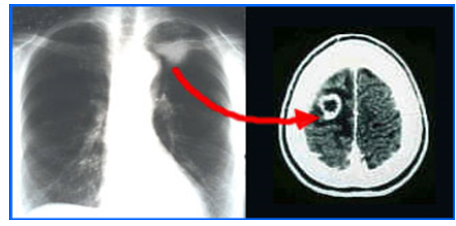

Chest X ray

Postero-anterior views were taken for all patients looking for any primary lesions that could originate from the chest

Sign: They are summarized in (Table 8 & Table 9 ). CT Scan: This was done for all the patients, 9 of them without I.V contrast, and 16 of them with I.V. contrast enhancement. Ten patients (40%) have single brain metastases, and 15 patients (60%) have multiple brain metastases Fig.(3.6) .In the 10 patients having single brain metastasis, the location [24,25] of the metastasis in relation to the brain was shown in (Table 10 ) and the relation of the primary origin of the tumor to multiplicity is seen in (Table 11 ). The density of the tumors was variable. 21 patients (84%) have solid tumors, and 4 patients (16%) have a cystic component of the tumor . The density of the solid tumors was isodense in 9 patients, hypodense in 7 patients, mixed density in 2 patients, and hyperdense in 3 patients

Enhancement of the tumor was seen in all the 16 patients in whom an I. V. contrast was used. 6 patients (37.5 %) showed ring like enhancement and 10 patients (62.5 %) showed heterogeneous enhancement.Perifocal edema was noticed in all the cases. It was marked in 6 patients (24 %), moderate in 15 patients (60%), and mild in 4 patients (16%). The metastases were supratentorial in 14 patients (56 %), infratentorial in 5 patients (20%), and both supraand [26,27,28] infratentorial in 6 patients (24%). Hydrocephalus was seen in 5 patients (20%), all of them have an infratentorial brain metastasis. It was due to compression of the 4thventricle by the metastasis leading to dilatation of the lateral and 3rd ventricles (triventricular hydrocephalus) (Figure 6 ).